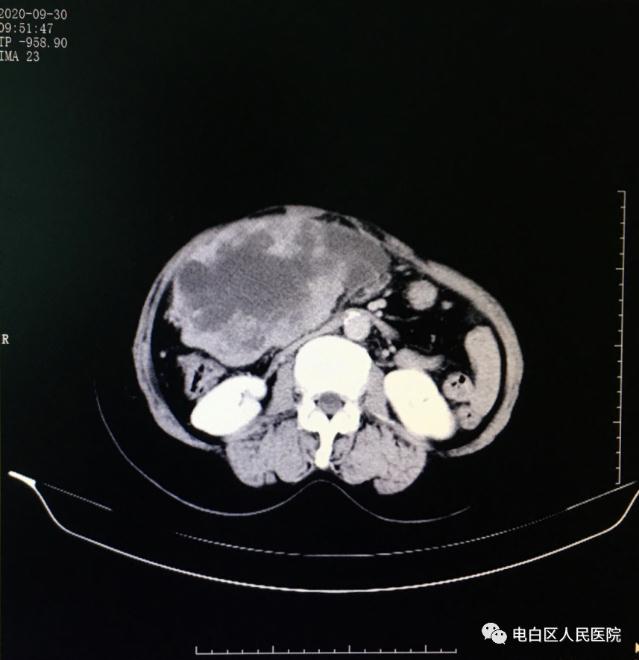

CT示肝區(qū)巨大占位

經(jīng)過充分的術(shù)前準(zhǔn)備,10月9日,在全麻下手術(shù)探查:術(shù)中發(fā)現(xiàn)肝臟超過25厘米巨大腫瘤,侵及肝S12345段,右肝S6亦有一1厘米結(jié)節(jié),考慮轉(zhuǎn)移灶。